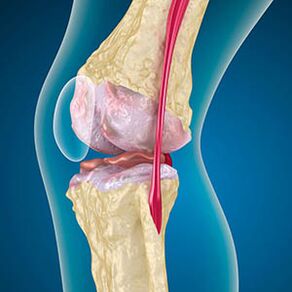

The osteoarthritis of the knee joint combines two processes: the destruction of the cartilage and the growth of osteophytes or bone spurs.The stage of the process is determined by the radiography.It is believed that osteoarthritis is the destruction of knee joints with age, the natural process of aging.The causes are muscle weakening and the poor blood supply to the fabric.How to be treated without surgery?Eliminate the factors that reduced muscle tone.

With osteoarthritis, the cartilage that covers the bones edges is abrasion or completely absent.Damaged tissue is not a source of pain, because it has no recipients.Inflammation in nearby structures causes characteristic symptoms.

The body continues the regeneration of damaged tissues, but the cartilage grows unequally.As a result, irregularities that damage other elements of the articulation are formed.The nature of the osteophytes is explained by compensation for the cartilage of smooth joints.Another version indicates that the growth of "spurs"It is associated with an attempt to stabilize medial or lateral joint due to muscle weakening.